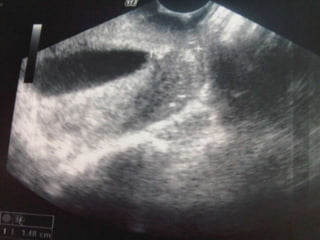

Se realiza USG en sala:

Se observa producto único de 190 g de 17 2/7 semanas

Longitud cervical de 1.48 cm